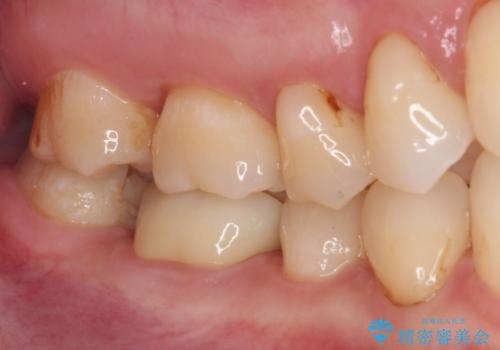

- セラミッククラウンが度々欠けてしまうとのことで来院された患者様です。

セラミッククラウンを装着するには、削る量がやや少ない印象であったので、クラウン破折リスクを回避するために削る量を少し増やすこととしました。

また、咬合力が強いため、強化セラミックのみで製作するフルジルコニアクラウンにて補綴治療することとしました。

フルジルコニアクラウンは、強度が高い反面、審美性に欠けるため、前歯部に装着することはお勧めできません。